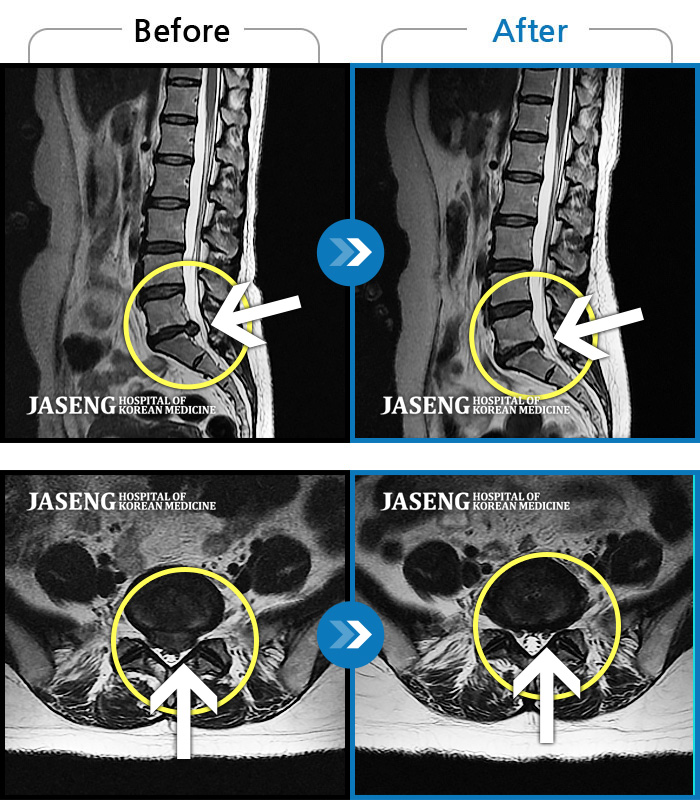

7월 중순경 허리디스크때문에 걷지도 앉지도 못하고 잠도 못 잘만큼 고통 이 심했는데 침과 추나요법 치료를 받고 지금은 통증없이 잘 지내고 있습니다...

친절하게 잘 치료해주신 김 민수 원장님께 감사드립니다~~